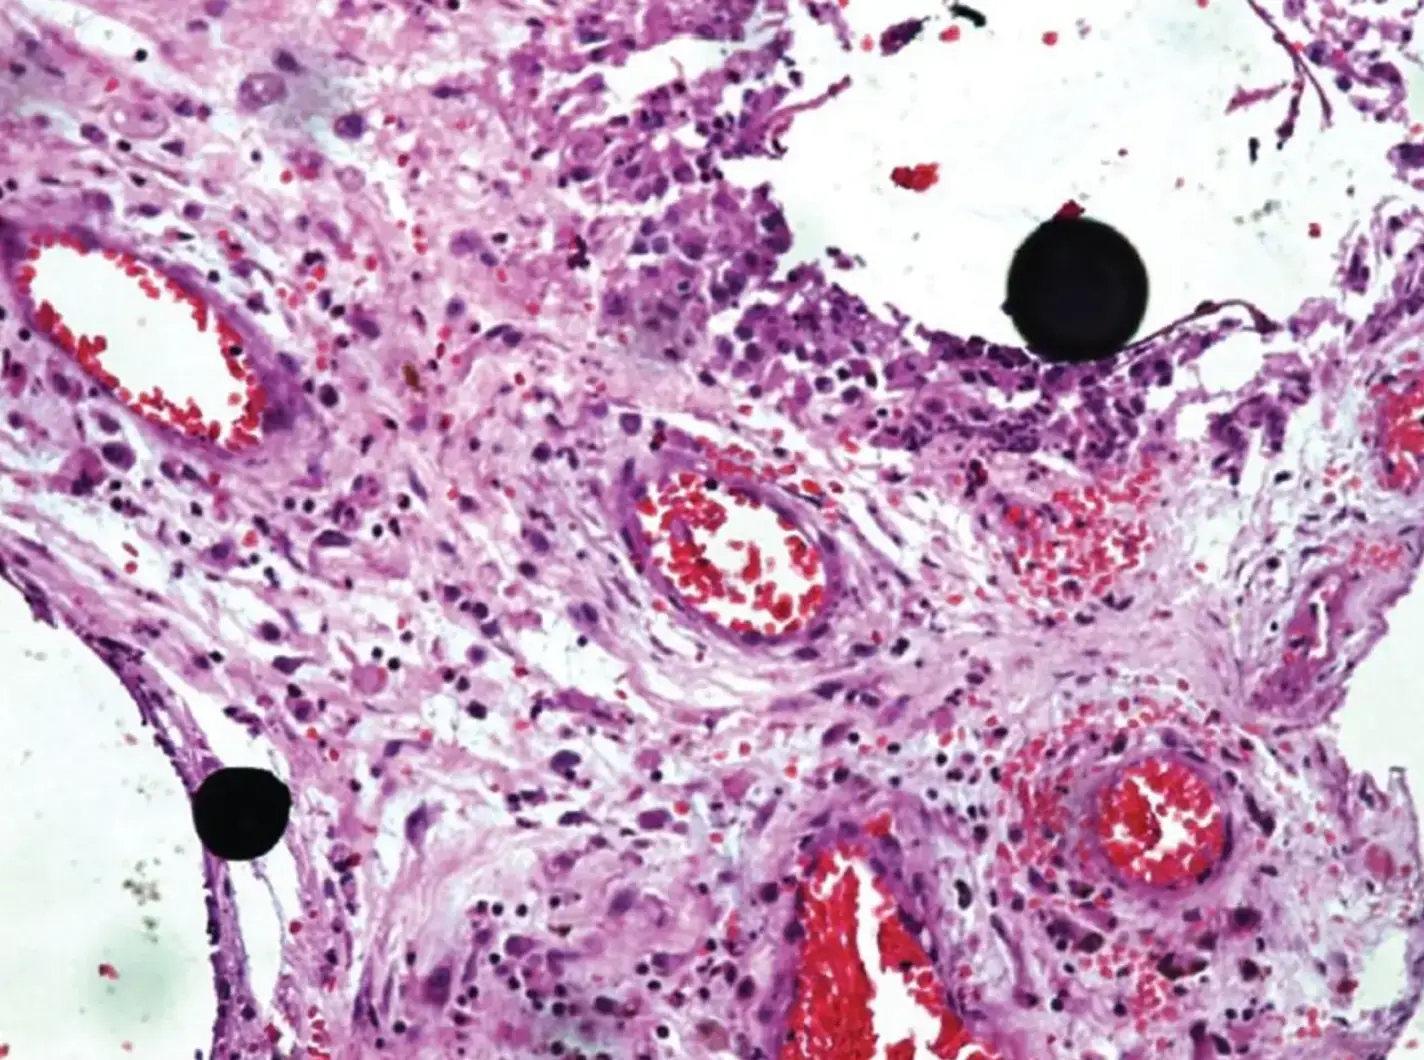

The report states: "The patient did not develop clinical signs of chronic poisoning, proving that subcutaneous mercury injection has a low risk of systemic toxicity, and that histopathology plays an important role in diagnosis."